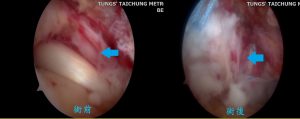

經檢查後發現患者右肩疼痛的原因,是旋轉肌袖退化破裂所導致,患者有肩部疼痛、手臂無法上舉等症狀,梁哲翰醫師建議進行微創肩關節內視鏡肌腱修補手術,修補破裂的肌腱並去除相關的骨刺,避免破裂越來越大而增加日後手術治療的困難度。患者手術後復原良好,微創傷口小,術後疼痛程度也較少,術後兩天即出院返家休養。術後經過三個月的門診追蹤,右手已恢復至昔日情況,疼痛已緩解而手臂無力的狀況也完全消失。